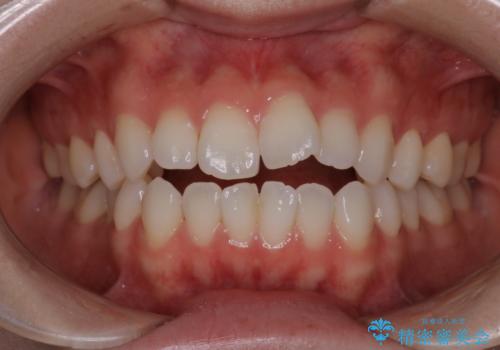

[マルチブラケットで後方移動] ワイヤー矯正で行う噛み合わせの改善